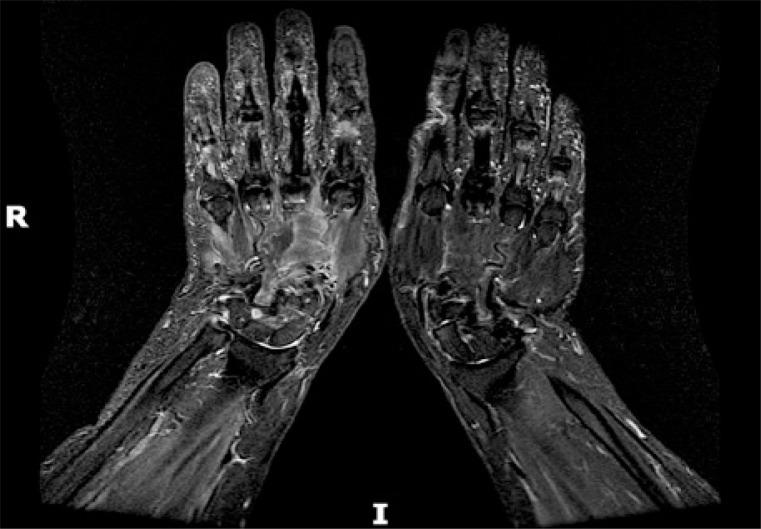

Among the rheumatic diseases whose symptoms are more often associated with the possibility of cancer and other malignancies are systemic sclerosis, dermatomyositis and rheumatic polymyalgia. However, a differential diagnosis should be performed in each case of non-typical rheumatic disease and/or other neoplastic disease risk factors. The article's aim was based on a literature review of this subject and presentation own a case description and discussion about arthritis as a paraneoplastic syndrome. The conclusions of our analysis were as follows: more often paraneoplastic arthritis occurs in men, in ages higher than 50 years old, in patients who poorly respond to treatment of arthritis with polyarticular symmetrical involvement of the limbs, seronegative type of inflammatory joint disease. In this group of patients, complete remission after treatment of the primary tumor and recurrence of the symptoms in the presence of metastasis was observed.

在症状更常与癌症及其他恶性肿瘤可能性相关的风湿性疾病中,有系统性硬化症、皮肌炎和风湿性多肌痛。然而,对于每一例非典型风湿性疾病和/或其他肿瘤性疾病风险因素的病例,都应进行鉴别诊断。本文的目的基于对该主题的文献综述,并呈现了一个关于关节炎作为副肿瘤综合征的病例描述及讨论。我们的分析结论如下:副肿瘤性关节炎更常发生于男性、50岁以上人群、对四肢多关节对称性受累的关节炎治疗反应不佳的患者、血清阴性类型的炎性关节病患者。在这组患者中,观察到原发性肿瘤治疗后完全缓解以及出现转移时症状复发的情况。